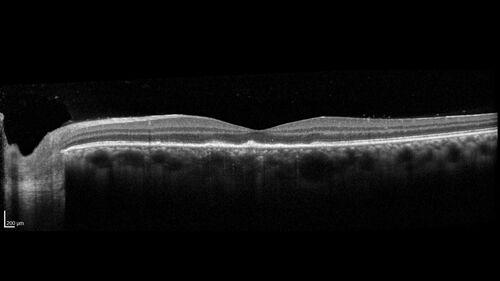

Syphilitic Chorioretinitis

41 year old man with vision loss for five days left eye. VA 20/32, 20/200